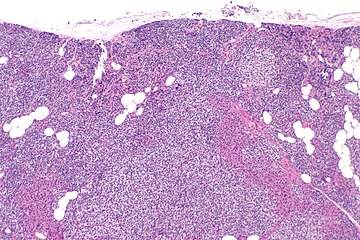

Parathyroid hyperplasia low mag.

Primary hyperplasia of the parathyroid gland, results from both hypocalcaemia and increased phosphate levels by decreasing expression of calcium sensing receptors and vitamin D receptors at the parathyroid gland.[8][4] These decreases in receptor expression lead to hyperfunctioning of the parathyroid. Hyperfunction of the parathyroid gland is thought to exacerbate primary hyperplasia which evolves further to a secondary more aggressive hyperplasia. Histologically, these hyperplasic glands can be either diffuse or nodular.[24] Primary hyperplasia, usually resulting in diffuse polyclonal growth is manly related to reversible secondary hyperparathyroidism. Secondary hyperplasia of the parathyroid gland is more often a nodular, monoclonal growth that sustains secondary hyperparathyroidism and is the catalyst in the progression to tertiary hyperparathyroidism. Nodular hyperplastic glands in tertiary hyperparathyroidism are distinctly larger in both absolute size and weight up to 20-40-fold increases have been reported.[25][26][24]

Parathyroid glands are normally composed of chief cells, adipocytes and scattered oxyphil cells.[27][14] Chief cells are thought to be responsible for the production, storage and secretion of parathyroid hormone. These cells appear light and dark with a prominent Golgi body and endoplasmic reticulum. In electron micrographs, secretory vesicles can be seen in and around the Golgi and at the cell membrane. These cells also contain prominent cytoplasmic adipose.[27][14] Upon onset of hyperplasia these cells are described as having a nodular pattern with enlargement of protein synthesis machinery such as the endoplasmic reticulum and Golgi. Increased secretory vesicles are seen and decreased intercellular fat is characteristic.[27][24] Oxyphil cells also appear hyperplasic however, these cells are much less prominent.[citation needed]